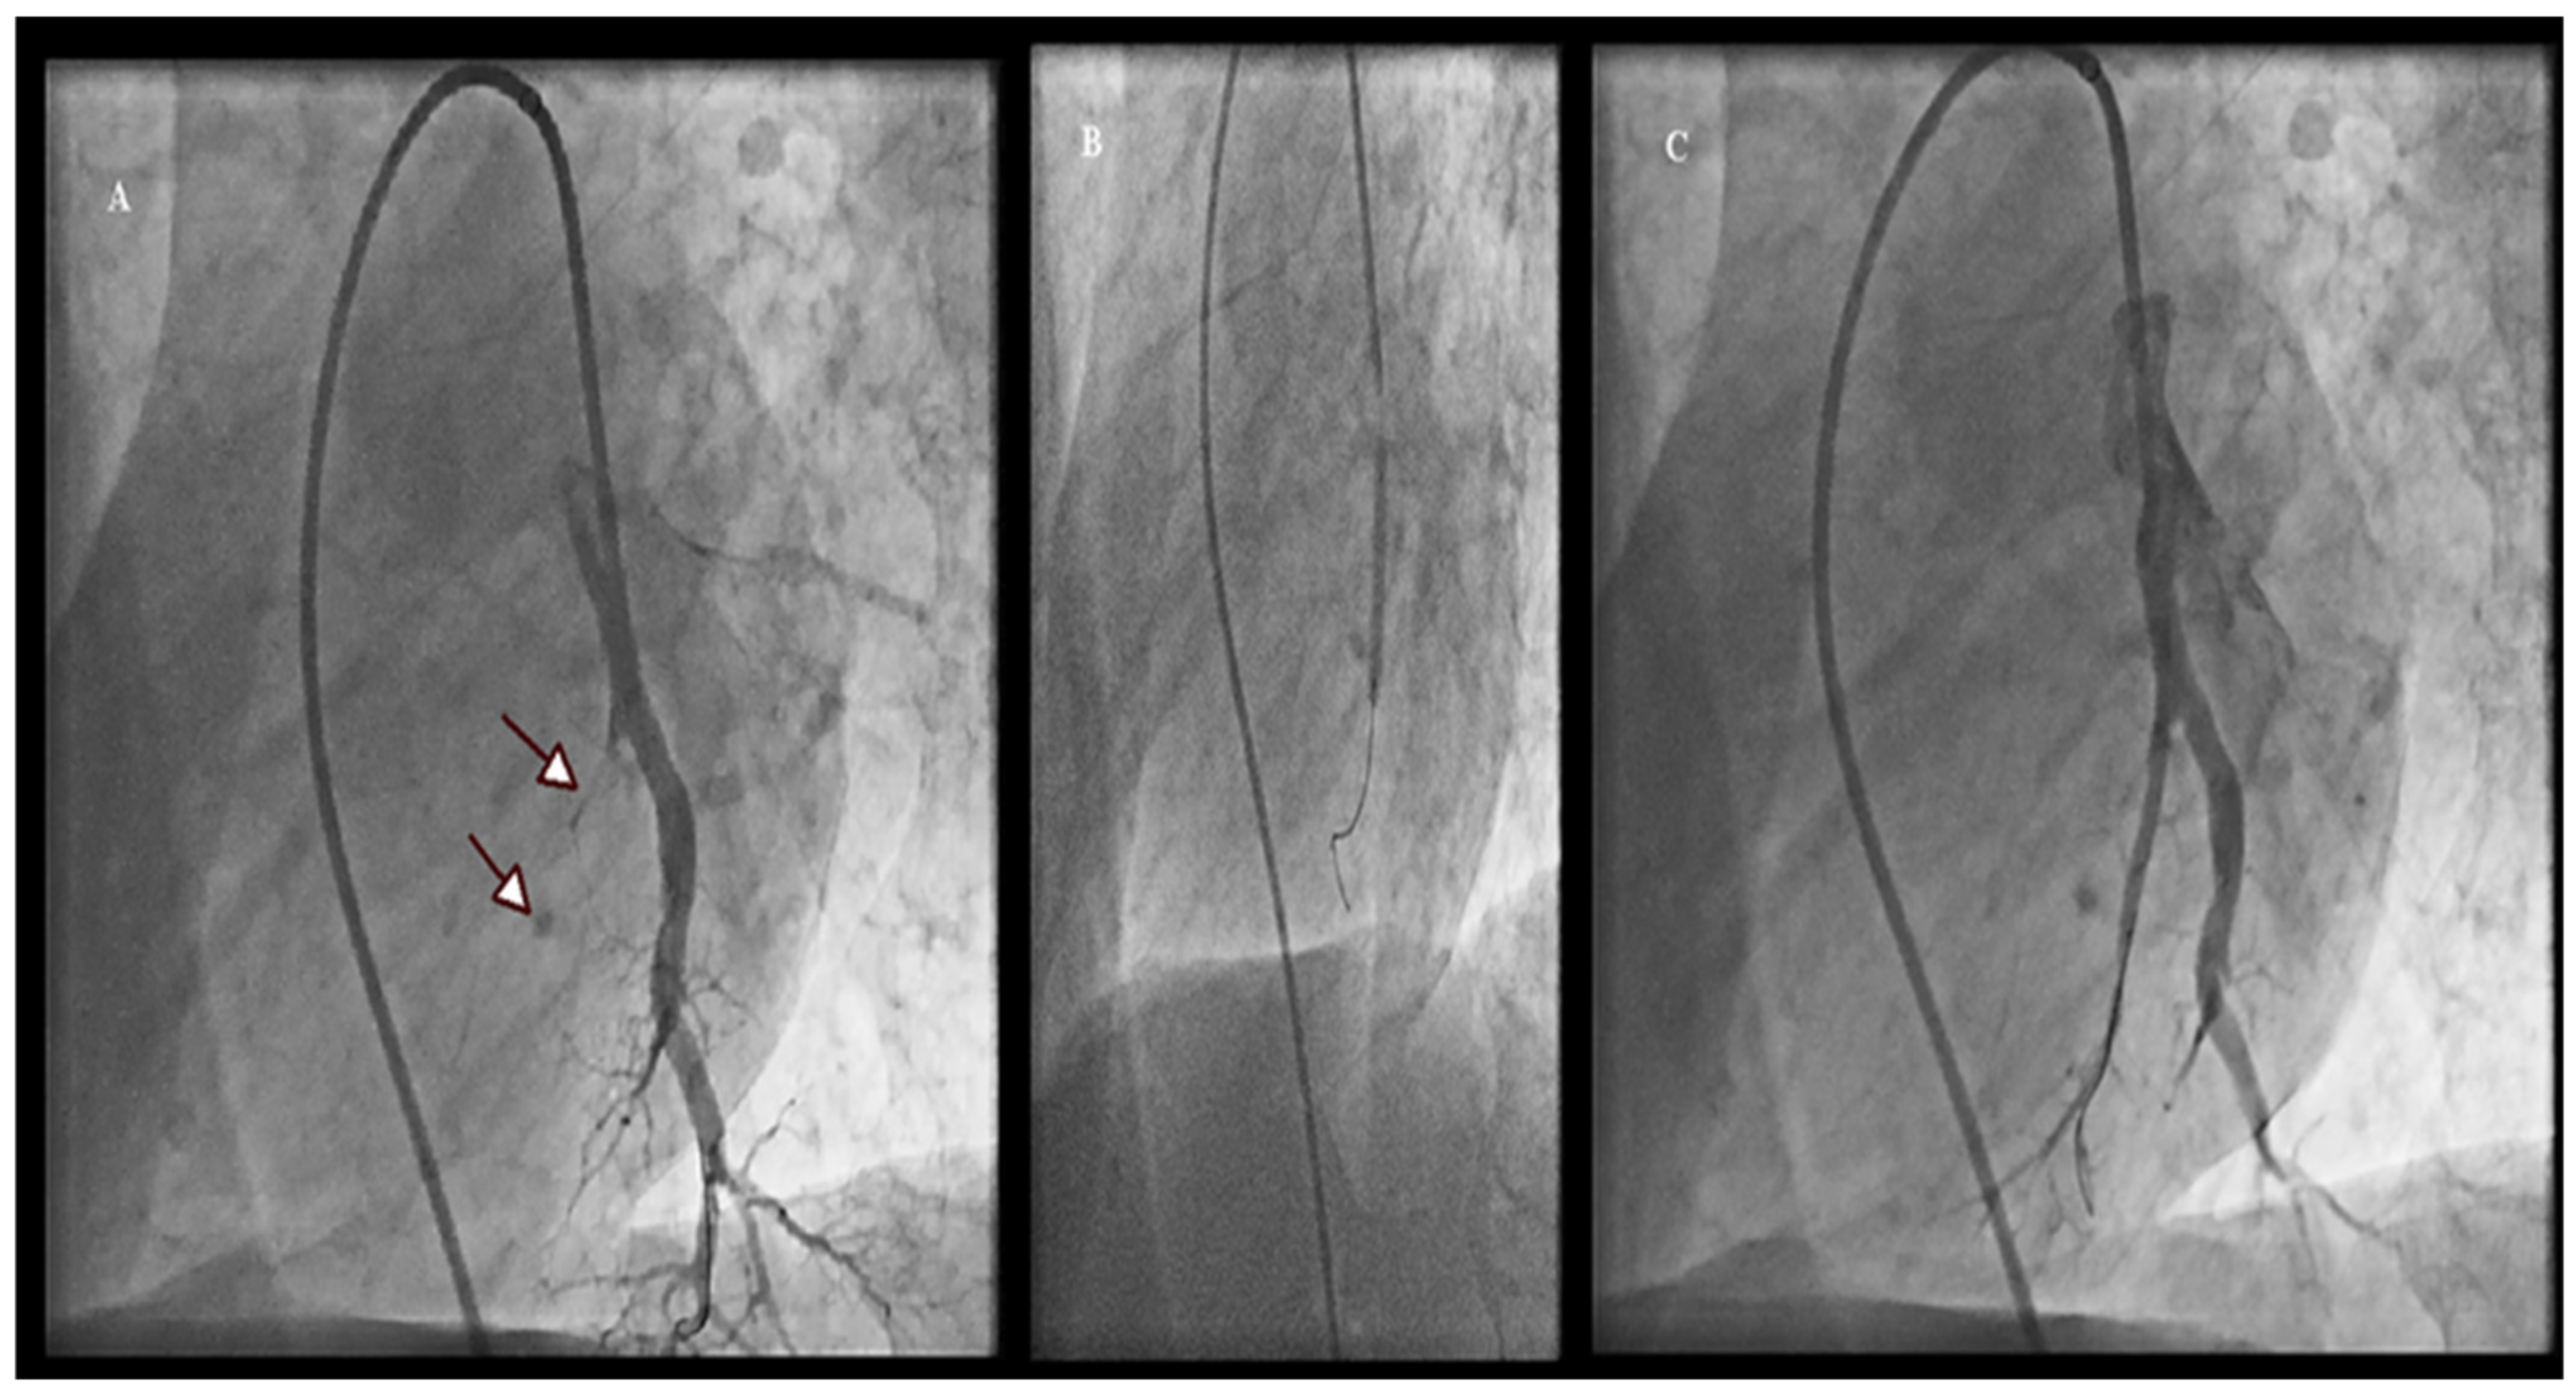

2.2. BPA Procedure